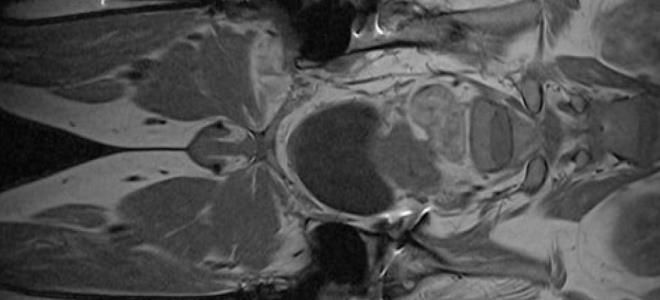

Расшифровка результатов МРТ малого таза является важным этапом в диагностике различных заболеваний и состояний, как у женщин, так и у мужчин. МРТ (магнитно-резонансная томография) позволяет получить детализированные изображения органов и тканей, что помогает врачам выявлять патологии на ранних стадиях.

Кроме того, результаты МРТ могут быть представлены в виде различных форматов изображений, таких как срезы, трехмерные реконструкции и функциональные изображения. Это позволяет врачу более точно оценить состояние органов и тканей, а также выявить даже незначительные изменения, которые могут указывать на наличие патологии.